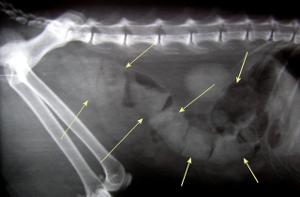

How can I prevent constipation in cats?

Cats have unique colon problems, especially with constipation and a problem called megacolon, where the colon stretches and can’t contract and expel the stool. The best thing is to be aware of any discomfort or straining when the pet passes stool. If the cat vocalizes, suddenly jumps out of the litterbox, or defecates in random areas about the house, these are early warning signs of a problem. Consult a veterinarian to prevent long-term colon problems. Changing how much fiber is in your pet’s diet can be helpful. Enemas and stool softeners are often recommended. If megacolon is present, surgical removal of the colon can be very helpful in allowing the cat to live a normal life.